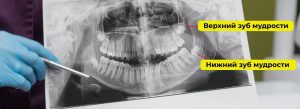

Исследование показывает состояние зубов, их корней и корневых каналов. Врач оценивает плотность и объём костной ткани, что особенно важно при планировании имплантации. КТ точно определяет положение ретинированных и дистопированных зубов, в том числе зубов мудрости, которые не прорезались или заняли неправильное положение.